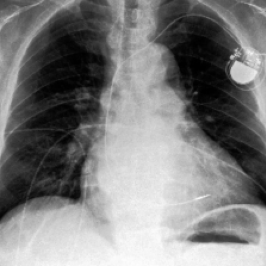

Waterbirds (Sagawa et al., 2020) is an image classification dataset where bird types are associated with a spurious background attribute (water or land). CelebA (Liu et al., 2015) is an image classification dataset, where hair color is an imbalanced attribute with respect to gender. MultiNLI (Williams et al., 2018) is a text benchmark of categorizing two sentences as entailing each other, contradicting each other, or neutral. The spurious correlation is between negation words like “never” and the “contradiction” label. CivilComments (Borkan et al., 2019) is a toxicity text classification dataset containing underrepresented demographic groups. CheXpert (Irvin et al., 2019) is a large-scale medical dataset of chest radiographs with rare pathologies, especially amongst certain minority groups.

We follow standard model choices and dataset splits consistent with prior work (Liu et al., 2021; Kirichenko et al., 2022; Qiu et al., 2023): for Waterbirds, CelebA, and CheXpert, we use ResNet-50 (He et al., 2016) pretrained on ImageNet1k (Russakovsky et al., 2015), for MultiNLI and CivilComments we use BERT (Devlin et al., 2018) pre-trained on Book Corpus and English Wikipedia data.

• J. Irvin, P. Rajpurkar, M. Ko, Y. Yu, S. Ciurea-Ilcus, C. Chute, H. Marklund, B. Haghgoo, R. Ball, K. Shpanskaya, J. Seekins, D. A. Mong, S. S. Halabi, J. K. Sandberg, R. Jones, D. B. Larson, C. P. Langlotz, B. N. Patel, M. P. Lungren, and A. Y. Ng (2019) CheXpert: a large chest radiograph dataset with uncertainty labels and expert comparison. External Links: 1901.07031, Link Cited by: §C.1, §5.1.